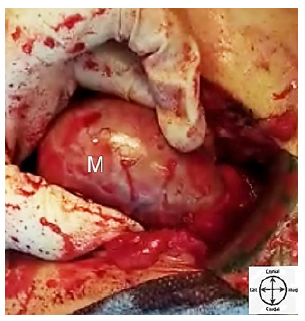

A 39 years old man referred to surgical emergent department with abdominal pain. He suffered from epigastric and preumbilical pain since the morning of the day he sought medical care. The pain classically shifted to the right iliac fossa as known in acute appendicitis. Nausea, vomiting and hyporexia were also present. Pain was reinforced by movement or coughing. He didn’t experience any identical abdominal pain previously in his life. He didn’t regularly smoke and denied drink alcohol or any psychiatric disorder. He had a controlled hypertension with daily single tablet of lozartan 25 mg. Prior surgical history was positive for right sided orchiectomy following unilateral right UDT in addition to left sided varicocelectomy. However, he denied premature born. The latter surgeries were performed when he was in his 29 years in one session. Retrospective review of his medical file revealed that the orchiectomy was completed in doubt; while a fat mass suspicious for hypotrophied undescended testicle had been resected from right inguinal canal by an urologist. Although gross pathologic report contained a gray piece of tissue measuring 5×1×1 cm, microscopic description revealed a fat tissue contained congested vessels and one fibrotic area resembling fibrotic testis, however, testicular tissue was not seen. Additionally postoperative abdominopelvic imaging report after orchiectomy was otherwise normal with no sign of intra-abdominal remained UDT. Patient was married and had a single healthy 8 years old girl. In systematic review patient mentioned low grade fever and hyporexia with no additional weight loss, respiratory symptoms, referral pain, hematuria, dysuria, or constipation in recent course of disease. Physical examination initiated beside the patient’s bed while he was laid and tended to not move. Although he was ill, the vital signs were completely normal. Abdominal examination was in lined with the diagnosis of acute appendicitis; means the presence of right iliac fossa point tenderness, rebounding pain, and positive rovsing sign. He was otherwise normal in physical examination. Laboratory data also implied on neutrophilic leukocytosis with absolute neutrophilic count 8.2×109/L. According to patient’s history and clinical findings he was prepared for emergent appendectomy with no extra imaging study requirement for diagnosis of acute appendicitis. In operating room, following the general anesthesia induction classic Mcburney’s incision on right iliac fossa was made. An assistant professor of general surgery, a general surgery chief resident and a licensed aid with operating room educational degree were present at the operating bed. After opening peritoneal layer slight reactive fluid was drained. The cecum was investigated and later the surgeon faced to appendix with inflammatory changes which was fixed to a retroperitoneal mass in its retrocecal location. Bundles were adhesiolyzed and primary appendectomy was completed. Then retrocecal mass with diameter of 6-7cm was examined. We primarily considered it as right dislocated kidney but intraoperative palpation of right kidney in its expected anatomical location ruled out our consideration. Therefore exploration of the mass from the same incision was proceeded. Figure 1 shows intraoperative view of the mass.

It was a white oval shaped soft mass with regular burden which contained single process originating from one of its pole remembered enlarged testicle. Figure 2 shows the mentioned objectives. Hence, intraoperative real-time urologic consult was performed through an internet connection with an experienced urologist. He was confirmed our diagnosis of that the mass was a remained intra-abdominal UDT. Foley catheter was introduced and no change was observed in urine characteristic after manipulation of the mass. The remained UDT had no invasions to adjacent structures grossly. Operation was continued with total right sided orchiectomy and finished without complication. Figure 3 shows the totally excised UDT. Pathologic study approved testicular tissue containing unifocal tumoral degeneration in lined with classic type of seminoma which was limited to testis with microscopic lymphovascular invasion around the epididymis.